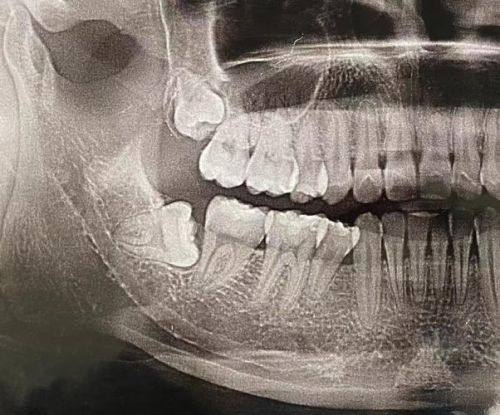

乐山艾诺口腔医疗美容诊所于2018年9月经市卫生计委批准成立,是一家正规的高端口腔专科诊疗机构。诊疗项目丰富,涵盖口腔美容、口腔修复、口腔种植、口腔正畸和口腔保健等。特色技术及优势显著,牙齿种植引进瑞士ITI、瑞典诺贝尔、韩国奥齿泰等流行种植系统,可个性化定制方案;牙齿矫正有美国隐适美、时代天使隐形矫正器;儿童齿科采用MRC肌功能矫正系统,花费低、疗程短。诊疗环境舒适,设有专精种植室、CBCT室等,还有VIP治疗室、休息室和候诊区。设备精良,如韩国原装进口的CBCT能快速严谨扫描口腔状况。虽然规模为微型企业,但医生技术从业多年非凡,口碑良好,致力于为患者提供高品质口腔服务。

1. 牙齿种植:引进瑞士ITI、瑞典诺贝尔、韩国奥齿泰等海内外流行、新进的种植系统,能根据客户的具体情况个性化定制种植方案,确保种植成效良好。